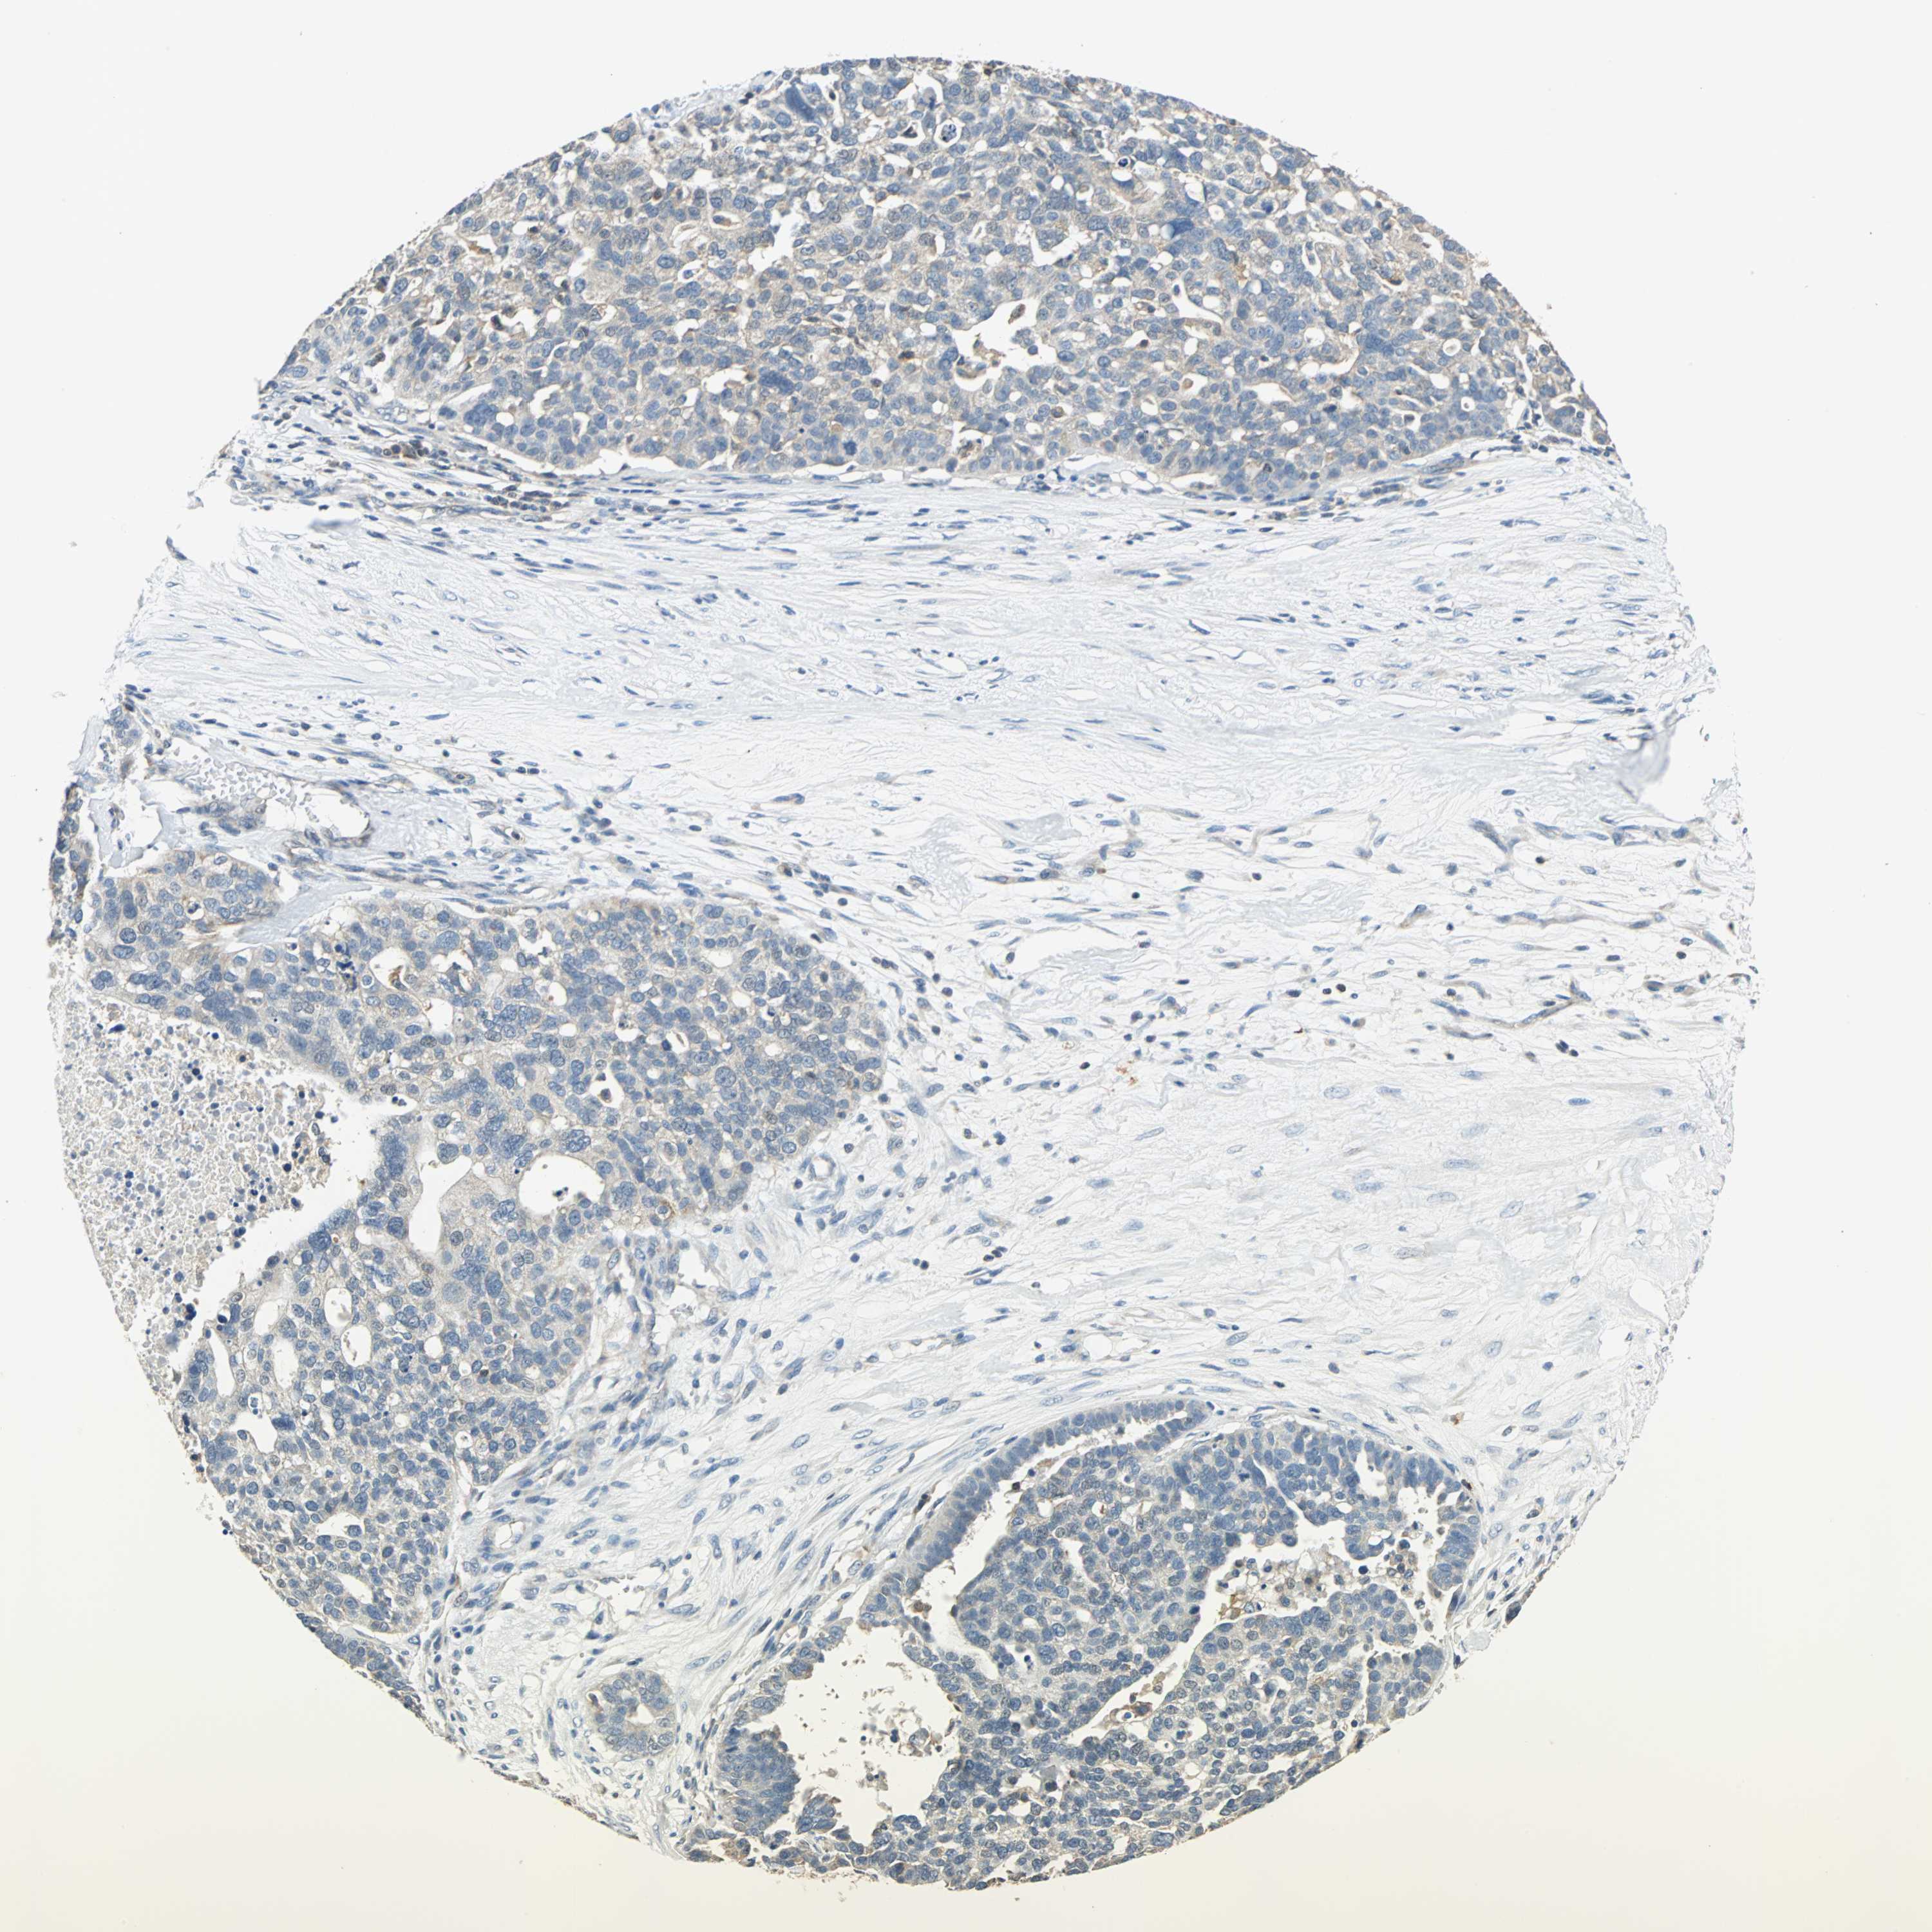

OVARIAN CANCER - Protein expressioni

A mouse-over function shows sample information and annotation data. Click on an image to view it in a full screen mode. Samples can be filtered based on level of antibody staining by selecting one or several of the following categories: high, medium, low and not detected. The assay and annotation is described here.

Note that samples used for immunohistochemistry by the Human Protein Atlas do not correspond to samples in the TCGA dataset.

Antibody stainingi

Antibody staining in the annotated cell types in the current human tissue is reported as not detected, low, medium, or high, based on conventional immunohistochemistry profiling in selected tissues. This score is based on the combination of the staining intensity and fraction of stained cells.

Each image is clickable and will lead to virtual microscopy that enables deeper exploration of all samples and also displays staining intensity scores, fraction scores and subcellular localization as well as patient and tissue information for each sample.

Antibody HPA006479

Antibody HPA008689

Antibody CAB020712

Cystadenocarcinoma, serous, NOS

Carcinoma, endometroid

Carcinoma, NOS

Cystadenocarcinoma, mucinous, NOS